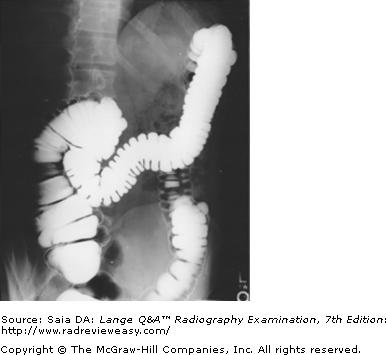

The radiograph pictured in Figure A may be used to evaluate

1. polypoid lesions.

2. the lateral wall of the descending colon.

3. the posterior wall of the rectum.

1 and 2 only